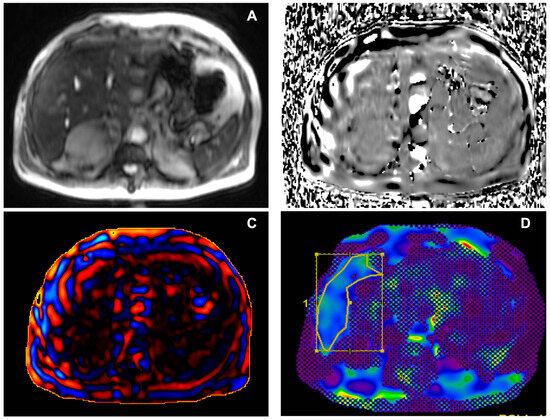

When performing MRE in obese patients, strategies aimed at increasing pad adherence (i.e., placement of additional elastic strap) might reduce technical failures; in addition, simple technical failures can be avoided in a trained team by checking the tube positioning before starting each examination. Other causes of failed elastograms were observed in the literature; Guglielmo et al. [5] described the following as important causes of low-quality elastograms: liver parenchymal diseases such as significant iron overload or severe steatosis. Iron overload generally results in a lower liver signal-to-noise ratio, with a non-diagnostic elastogram, as shown in Figure 4.

Figure 4. Male, 38 years old, with severe iron overload. (A) Axial phase image showing the absence of wave propagation through the liver. (B) Non-diagnostic wave image. (C) Elastogram reconstruction with the interposition of the 95% confidence map not covering the liver area. (D) Axial Starmap T2* breath-hold sequence, confirming iron overload. In the case of severe iron overload, an option might be to use SE echoplanar sequences instead of GRE sequences, with the latter being more prone to non-diagnostic MRE, even if an univocal cut-off of severe iron overload of MRE failure has not been established yet [37,38]. As observed by a retrospective study by Meng Y. et al. [39] on 1377 consecutive MRE examinations, MRE often had a low failure rate (5.6%), with the majority of failure cases due to inadequate signal-to-noise ratio related to iron overload (3%) and the remaining cases caused by execution errors or respiratory artifacts. A retrospective study by Wagner M. et al. [40] confirmed the higher rate of technical failure associated with liver iron overload with p < 0.001. Also, the presence of bowel interposition between the liver and abdominal wall, motion artifacts, or interfering paramagnetic materials are considered as causes of low-quality elastograms. Despite the lack of published data on the subject from our centre, the failure rate aligns with literature data after the initial eight weeks of training.